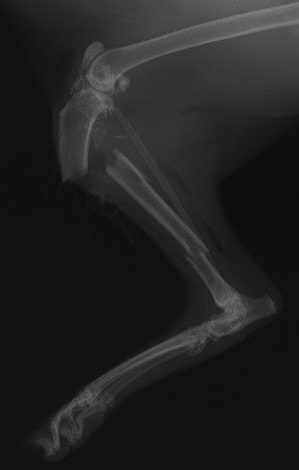

ペルシャ猫 11ヶ月齢 雄

他院にて左大腿骨遠位の成長板骨折(salter-harrisⅠ型)が認められており、治療相談を目的として来院。当院にて、キルシュナーワイヤーを用いたピンニングにより骨折部位の整復を行いました。術後の経過は良好で、現在も経過観察中です。

術前レントゲン

術後レントゲン